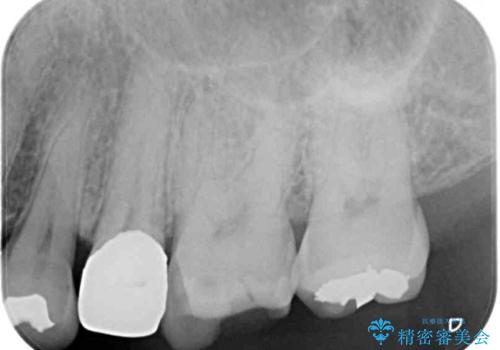

レントゲン写真より、既に根管治療がされている歯であり、根尖部に骨透過像が認められました。

特に症状はありませんでしたが、根管治療を希望されたため、まずは根管治療を行うこととしました。